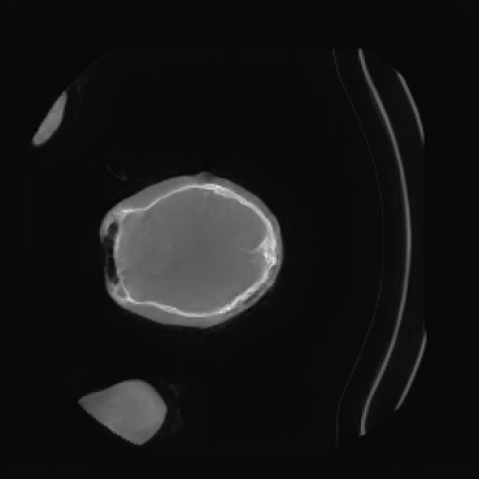

Appendix D More Generated Images Slices

![[Uncaptioned image]](x3.png)